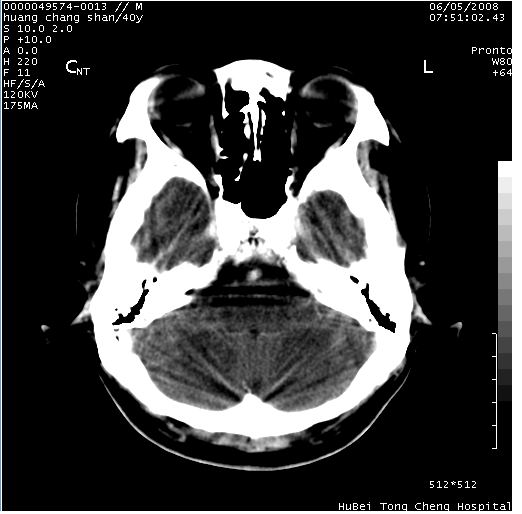

患者 m,40y。头痛,视力模糊,多饮多尿,性欲减退半年余。

行ct平扫+增强,图象如下:

结合临床考虑鞍上生殖细胞瘤可能性大于脑膜瘤(增强未见脑膜围征),建议结合冠状位扫描看病灶起源及垂体窝、鞍底情况。垂体窝内未见明显软组织密度影,垂体窝未见扩大,暂不考虑垂体瘤;病灶较大,未见囊变及钙化,颅咽管瘤不支持。期待结果!

4、鉴别诊断:脑膜瘤,瘤体内点状钙化最具特征性,常位于鞍结节。颅咽管瘤,蛋壳样钙化,常有囊变。动脉瘤,位于鞍旁,强化与动脉一致。有时尚需与发生于鞍区的生殖细胞瘤鉴别,生殖细胞瘤钙化亦较常见。

5、友情提示:下回发现鞍区占位性病变,最好加扫冠状位,了解肿瘤与蝶鞍的关系及蝶鞍骨质的改变。